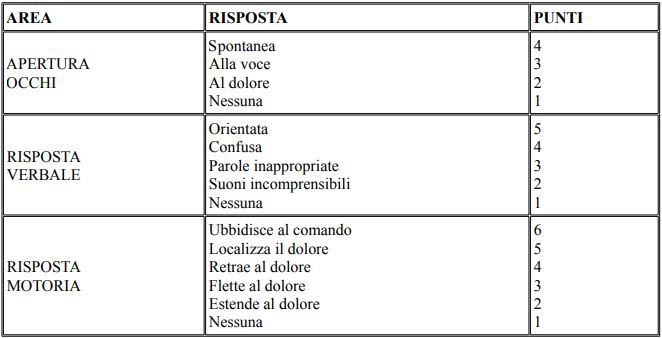

l medico d’emergenza valuta il soggetto vittima di un trauma cranico con un attento esame neurologico e anamnestico e l’utilizzo della scala di Glasgow (espressa con la sigla GCS Glasgow Coma Score) che gli permette di valutare lo stato di vigilanza. La scala valuta lo stimolo oculare, verbale e motorio ed è espressa con un punteggio che è la somma delle valutazioni di ogni singola funzione. Il massimo punteggio è 15 (soggetto vigile e senza sintomi) e il minimo 3 e indica un profondo stato d’incoscienza.

La scala di Glasgow

La scala di Glasgow permette inoltre al medico di valutare il danno cerebrale nel tempo e stabilire eventuali interventi diagnostici e terapeutici. Attraverso questo mezzo e la valutazione clinica, il trauma cranico può essere definito:

- Trauma cranico lieve o minore di grado 0 con GCS tra 15 e 14

- Trauma cranico moderato grado 1 con GCS tra 13 e 9

- Trauma cranico grave o severo grado 2 con GCS inferiore a 9